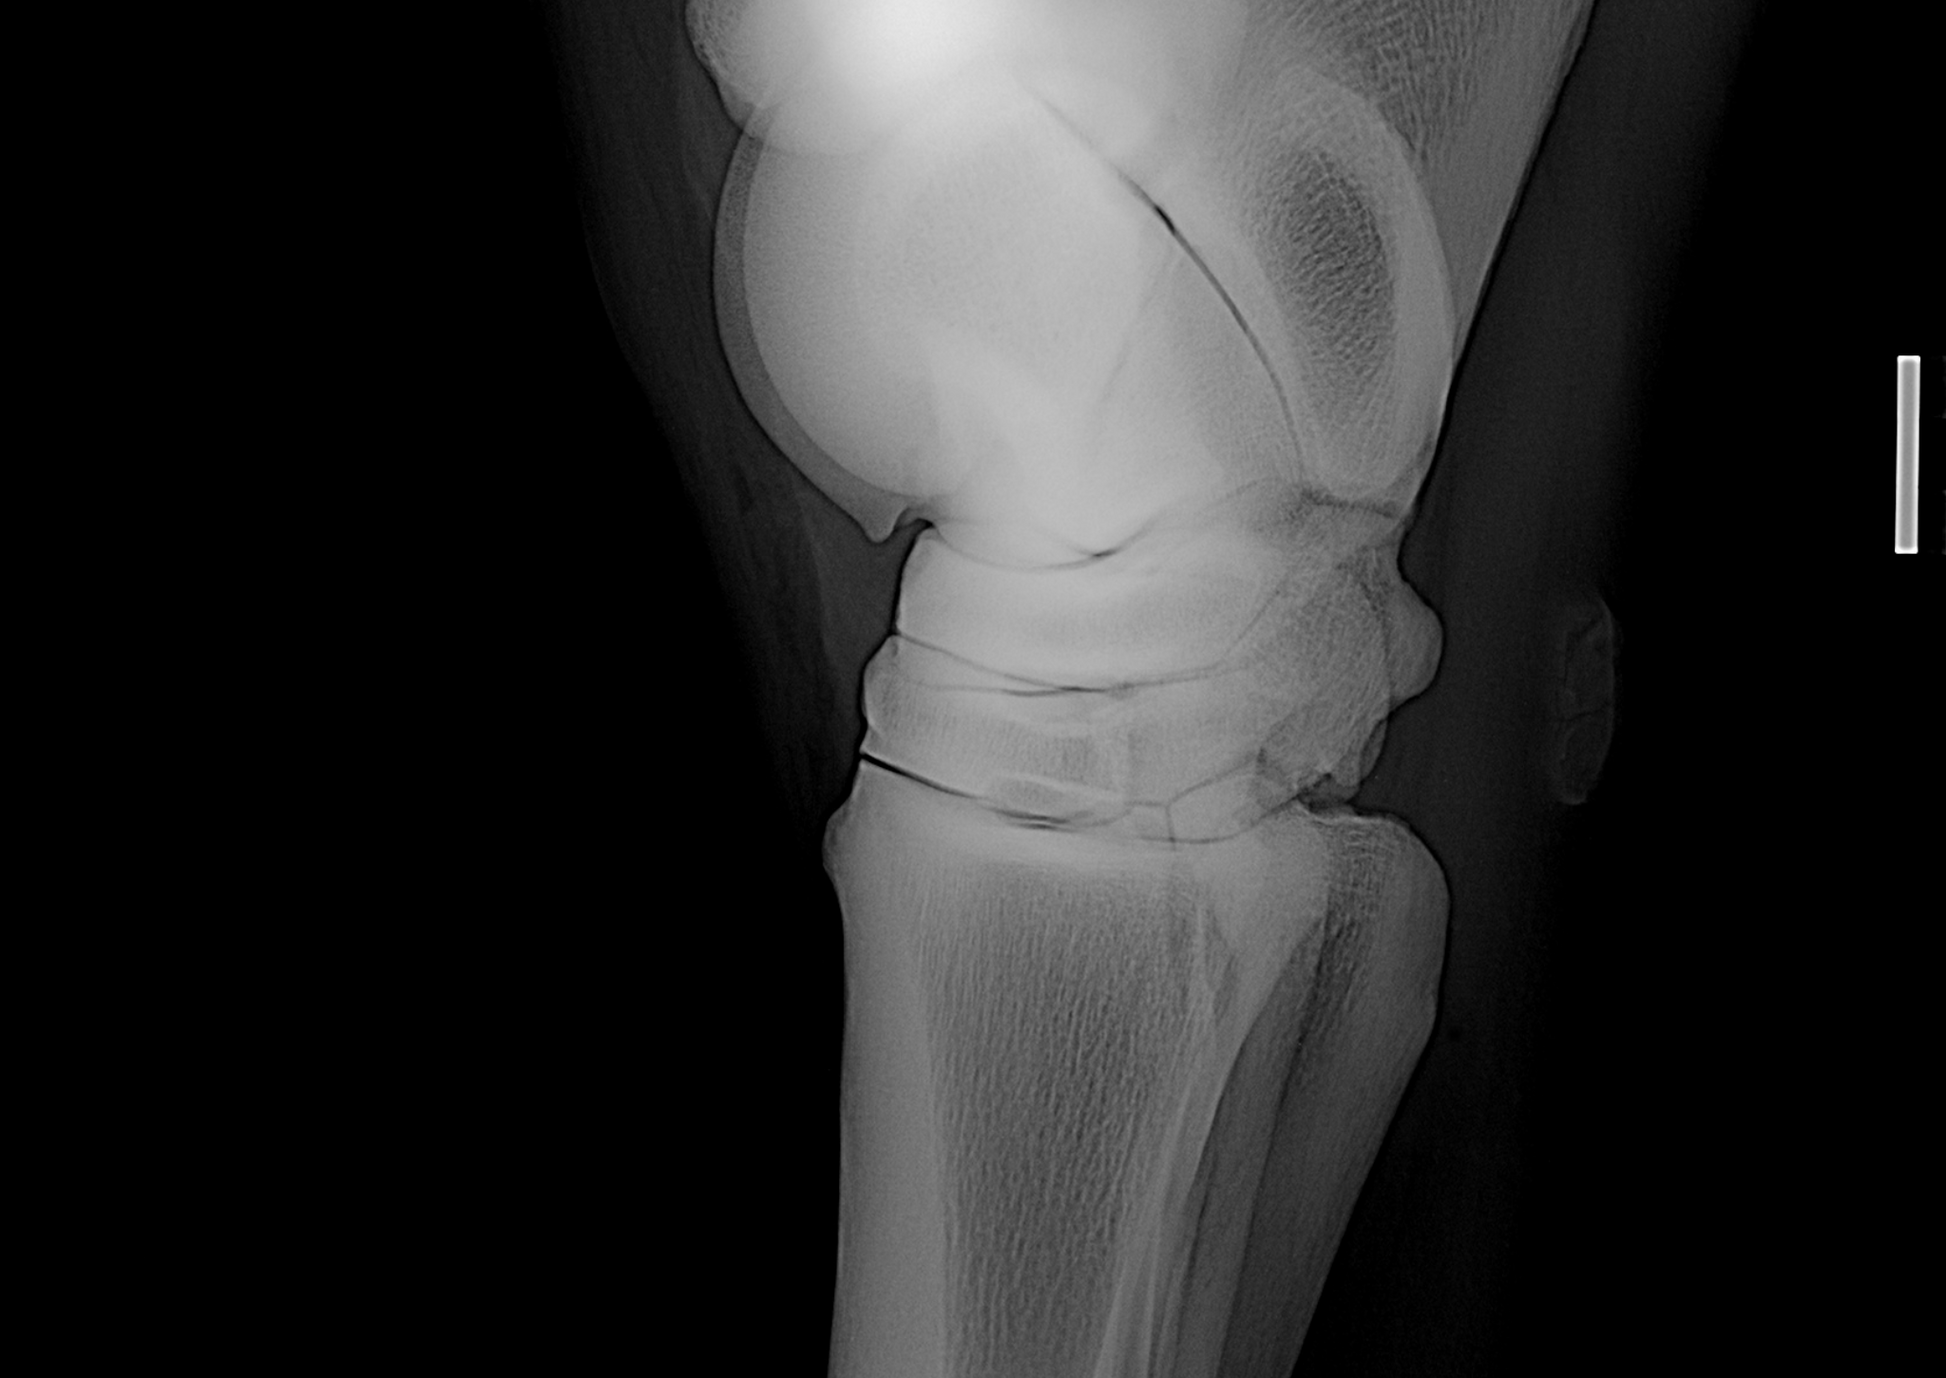

The Equine Stifle, an overview

Non-conventional radiographic views used in horses, including principles and examples, are discussed and presented.

Chair: Dr Rhiannon Morgan, BSc BVSc CertAVP MVetMed(Hons) PhD DipECVDI MRCVS EBVS, European Specialist in Veterinary Diagnostic Imaging Lecturer in Equine Diagnostic Imaging, Royal Veterinary College

Speaker: Dr Mélanie Perrier Diplomate, ACVS&ECVS CERP, Lecturer in Equine Surgery, Royal Veterinary College